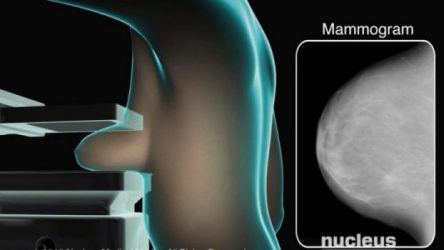

اولین ماموگرافی پستان

معمولاً در صورتيكه بيمار سابقه ای از سرطان پستان به صورت فاميلی نداشته باشد لازم است اولين ماموگرافی را از سن 40 سالگی شروع كند. در برخی موارد توسط جراح سرطان پستان توصيه می شود اولين ماموگرافی از سن 35 سالگی شروع شود و بعد در صورت نرمال بودن از 40 سالگی به بعد ادامه پيدا كند.